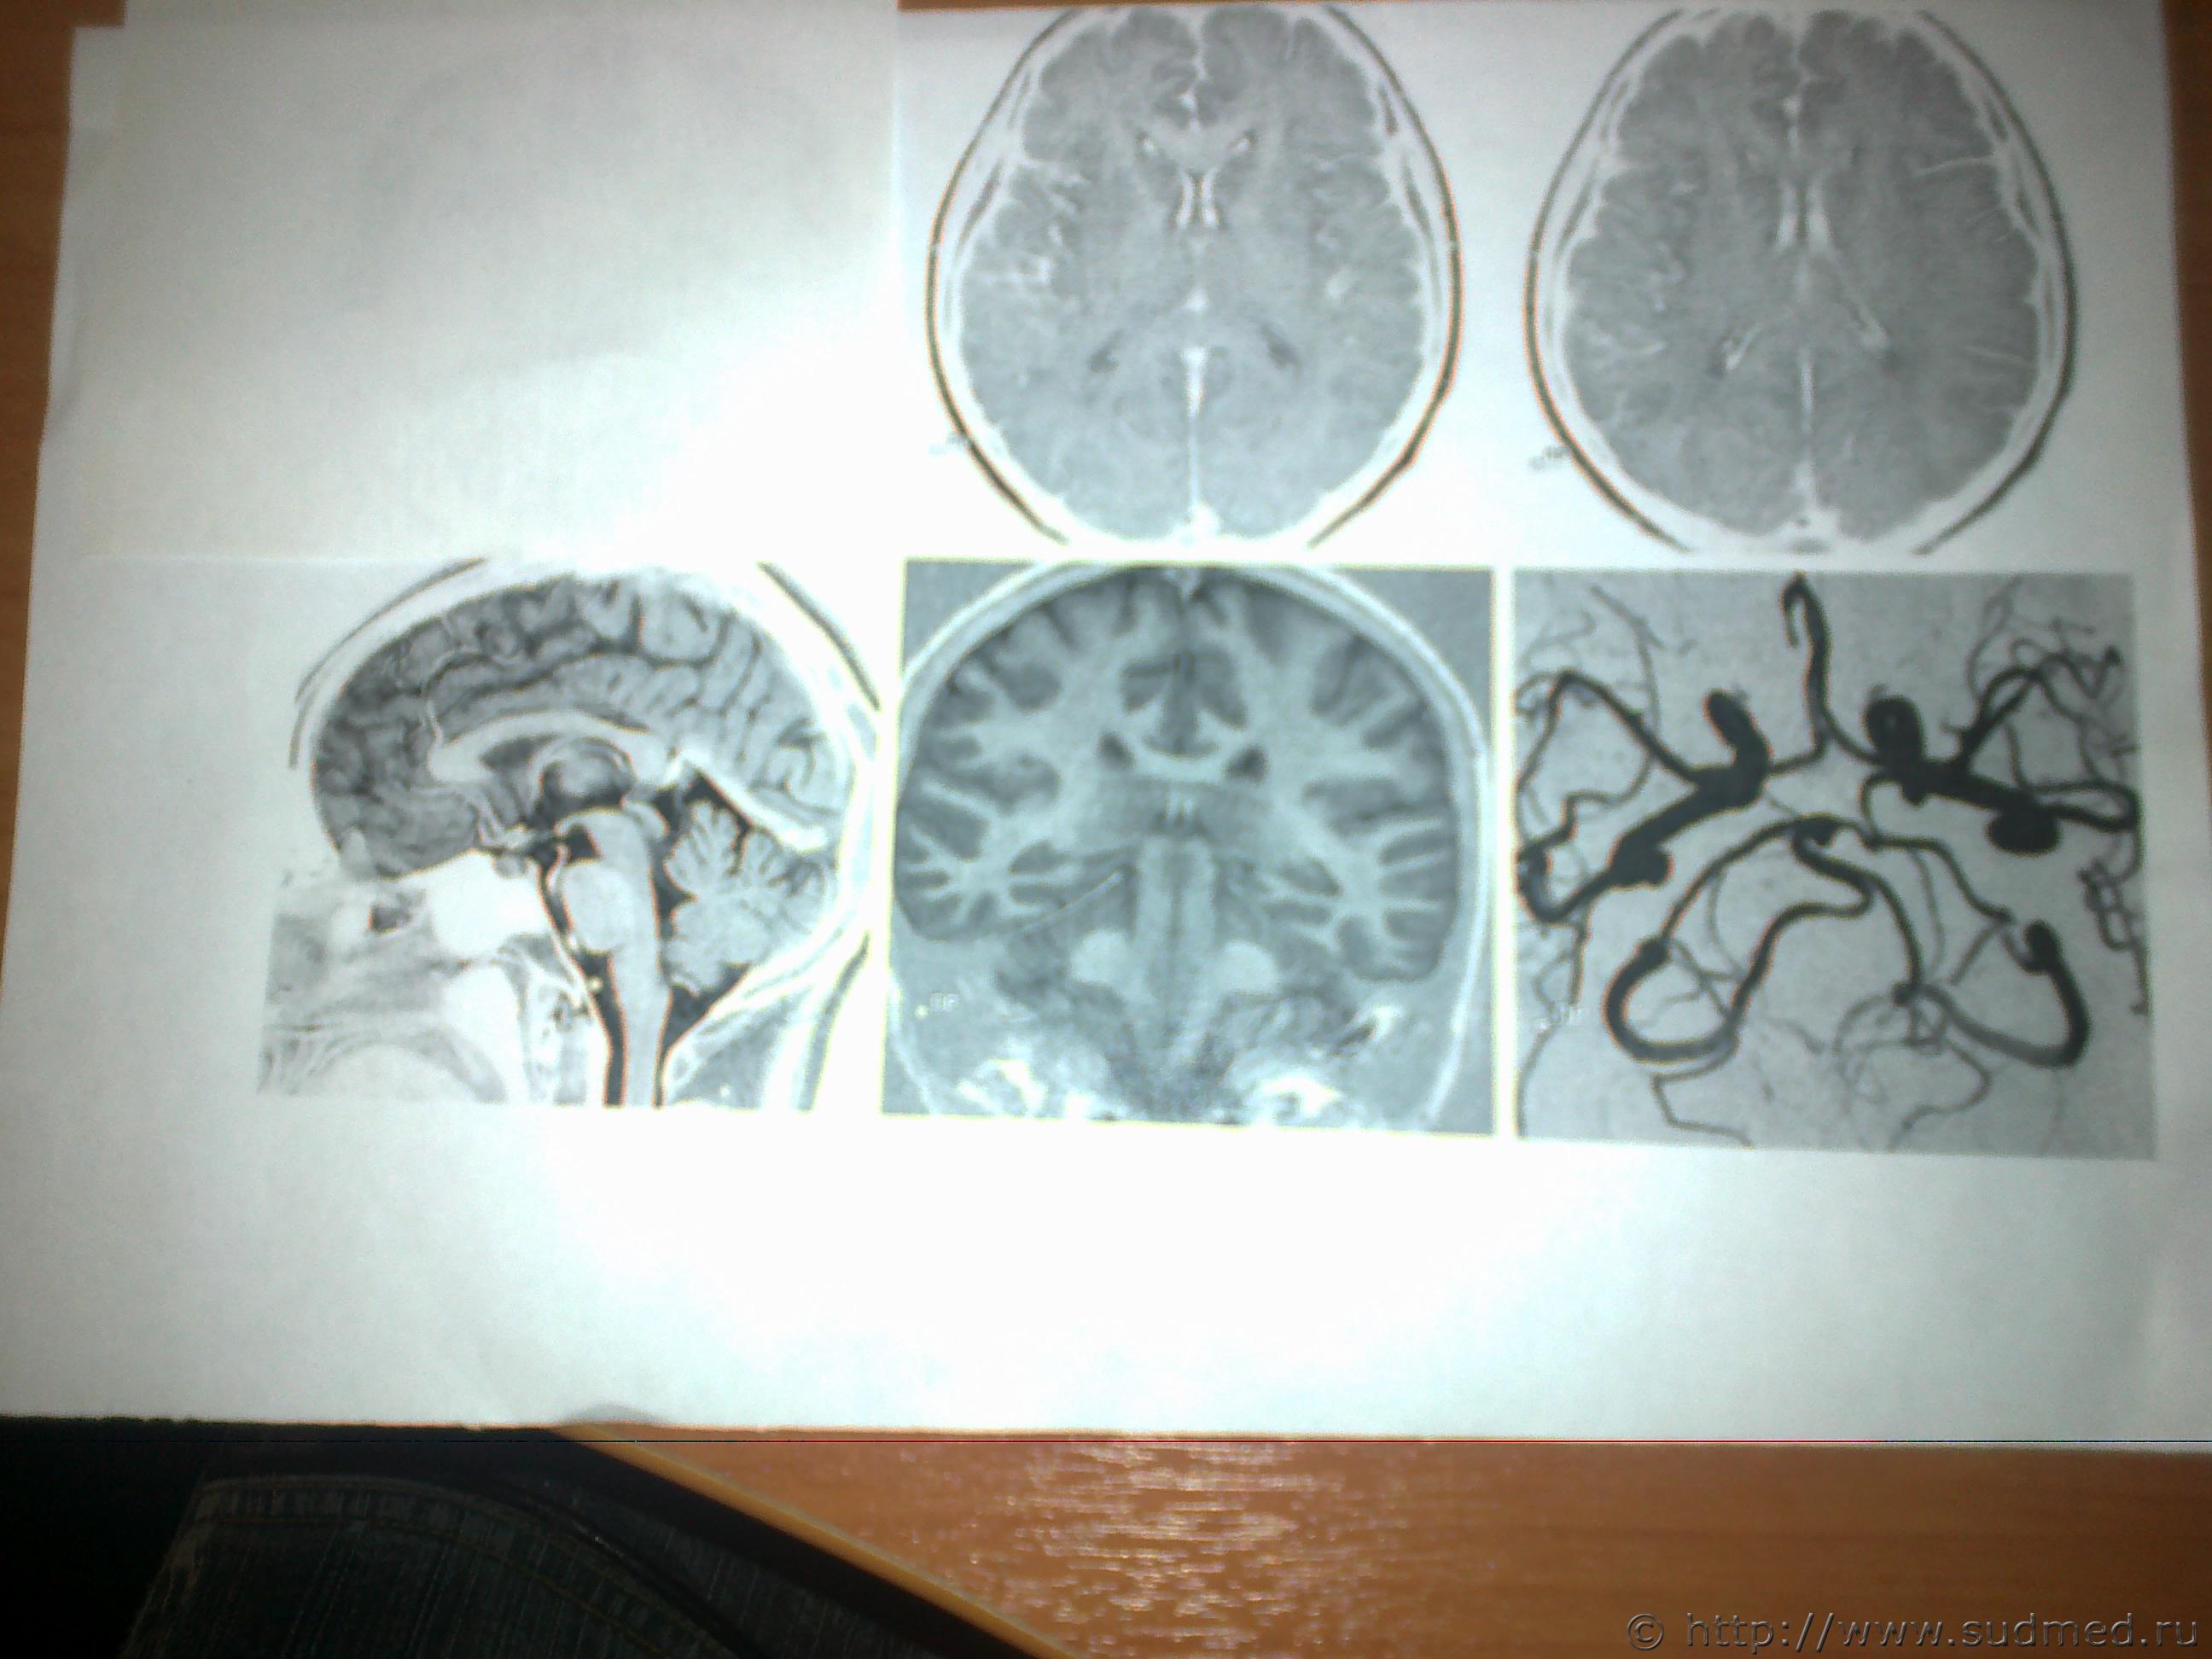

Есть заключение только на тему сотрясения общее и на листе где заключение отображены 6 снимков где как раз затылочную часть совсем не видно. Заключение пишу: Объёмных, очаговых или структурных патологических изменений головного мозга и сосудов его артериального круга не выявлено. про кости черепа в направление на мрт не указывалось от сюда и уклон на мозг. снимки на которых написано заключение прилагаю в том виде как они есть на листе бумаги. Те что предоставила ранее, с диска, просто сфотографировала на телефон по ним нет заключения и костей тема не затрагивалась в направление на мрт.

Светичок! Надо показать сами эти снимки специалисту по МРТ (на пленке и/или на электронном носителе. На эл.носителе даже лучше, т.к. на пленке могут быть распечатаны, к примеру, 30 сканов, а, фактически, их 150 было выполнено и все они могут быть представлены Вам на диске или на флешке). Присланное Вами хуже по качеству, чем снимки, которые есть фактически и, на этом форуме, насколько мне известно, нет врачей имеющих сертификат по специальности"Рентгенология" и дополнительную специальную подготовку по ядерно-магнито-резонансной томографии. Поищите какой-нибудь форум рентгенологов, вероятно, там смогут дать более компетентные комментарии. Насколько я разбираюсь в МРТ (немножко): на снимках №1, 2 и 3 - вероятнее всего, ликворная киста. Возможно, это вариант развития, возможно, след от давно регрессировавшей (прошедшей, рассосавшейся) гематомы. В любом случае, даже если это изменение имеет посттравматическое происхождение, то травма была давно (месяцы или годы назад), на что указывает отсутствие признаков внутричерепной гематомы, перифокального отека вещества головного мозга. Только по этим снимкам ни один специалист не сможет серьезно и аргументированно доказать, что это: 1.именно последствие травмы и ни что другое, 2.точно установить дату этой предполагаемой травмы. (Просьба не путать специалиста с шарлатаном, который, "все что угодно за ваши деньги" - в суде такое "заключение" окажется несостоятельным). На снимках №4 и 5 - шов между затылочной и теменными костями, №6 - каналы диплоэтических вен (вены, проходящие сквозь кости черепа. Они извитые, а перелом, в такой проекции выглядит как прямая линия, перпендикулярно и косо-перпендикулярно пересекающая кость свода черепа). МРТ - неоптимальный метод для оценки состояния костей свода черепа (МРТ - великолепный метод для оценки состояния мягких тканей). Гораздо лучше - обычная рентгенография костей свода черепа. Желательно,сделанная на современном цифровом рентгеновском аппарате. Желательно - полипозиционная (т.е. не только стандартные снимки в прямой и одной из боковых проекций, а, в данном случае - прямая проекция,правая и левая боковые проекции, контактная рентгенограмма затылочной кости и, возможно, снимок с выведением места предполагаемого перелома в краеобразующую зону. Тогда на 100% будет понятно,что это такое. Вероятно, на 100% будет понятно уже на стадии рентгенограмм в прямой и боковых проекциях. Грамотный рентгенолог знает все это лучше, чем я тут написал). Можно, конечно, сделать мультиспиральную компьютерную томографию /МСКТ/ в костном режиме с 3-D реформацией изображения,однако, лучевая нагрузка будет больше, а информативность - сопоставимая. Если в итоге найдется что-то похожее на посттраматические изменения, то нужно будет провести исследование всех рентгенограмм, которые выполнялись непосредственно после конкретной травмы, если когда-то до неё делались рентгенограммы, МРТ, КТ головы - их тоже. Это уже задача судебно-медицинской экспертизы. + будут учитываться данные медицинских карт и прочие документы о лечении после этой травмы, о состоянии здоровья до неё и т.п., т.к. перелом кости/костей свода черепа, внутричерепная гематома протекают с весьма выраженной клинической симптоматикой (от чего-то "легкого" и похожего на "сотрясение головного мозга" до тяжелых невропатологических проблем).